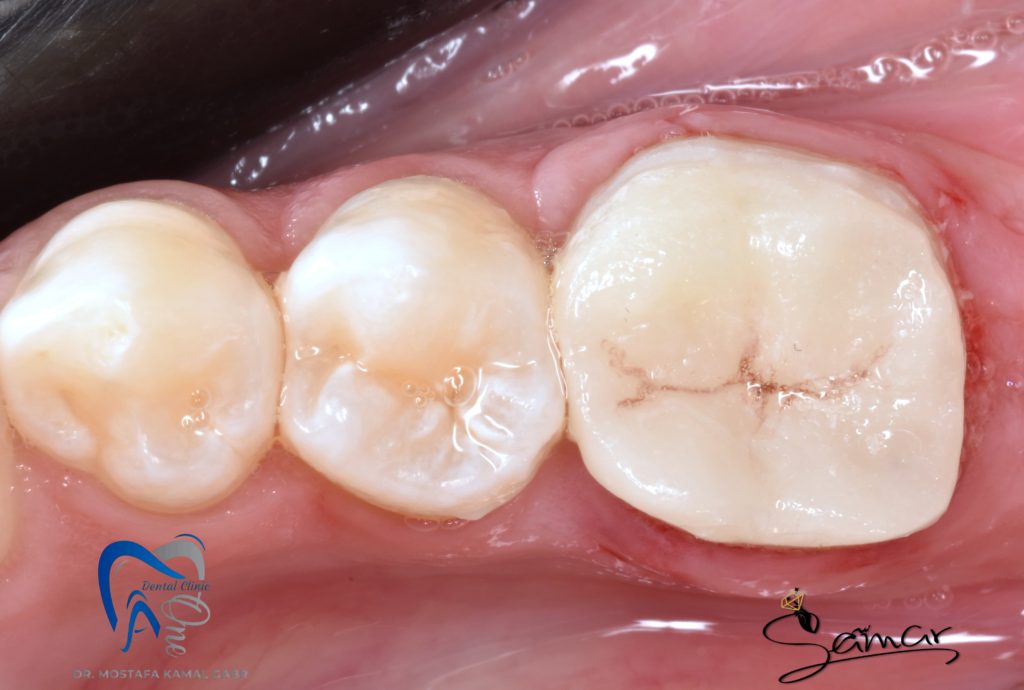

After many time of CDD application

After IDS and resin coat using high filled flowable composite

then follow up period of 3 months before final extarcronal restoration